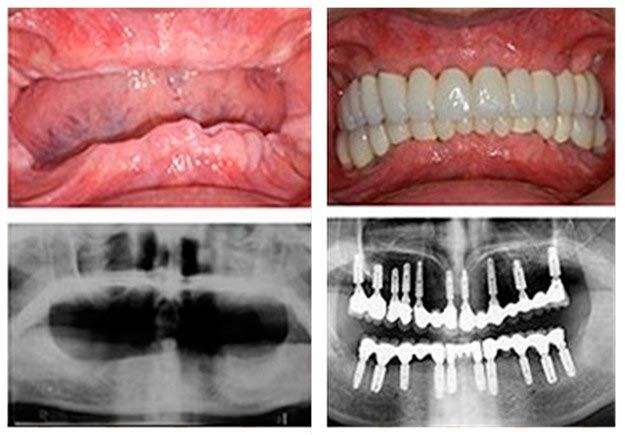

圣洁口腔技术推荐——全口种植牙使用麦芽ALL-ON-4即刻负重技术会更好。当天即可恢复饮食。

All-on-4即刻负重技术更好、更快、更省!

好:北京知名专家领衔,4颗种植体,种出整排牙

快:全口/半口牙齿缺失,1个小时种出半口好牙

省:种植导板技术,无需切开牙龈,更省钱,半口牙省下1/3费用